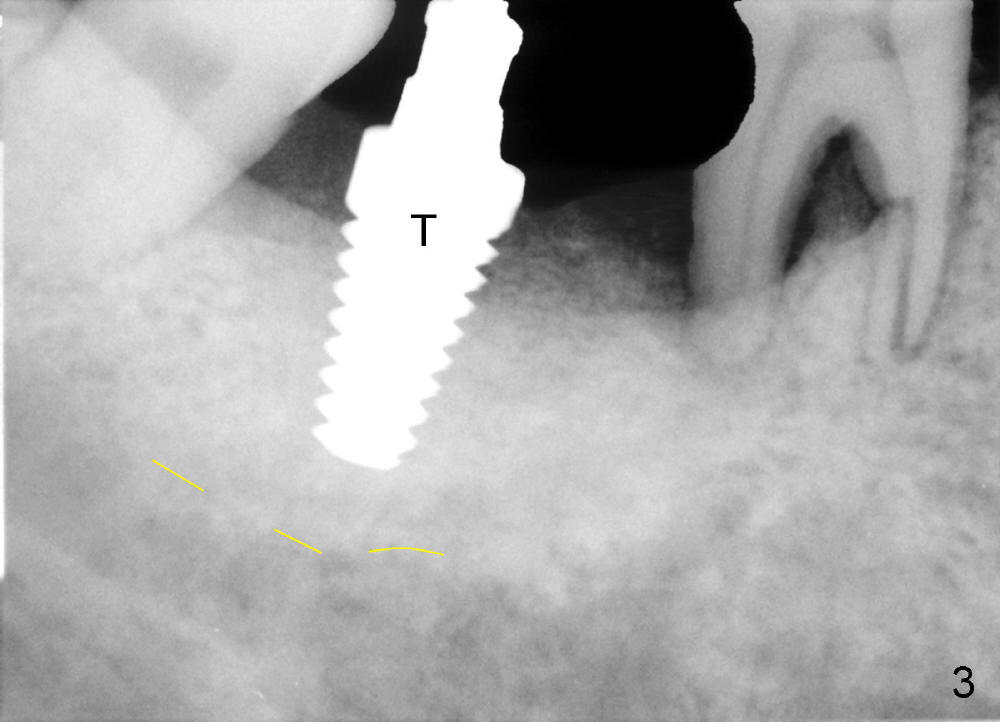

Luckily the patient returns for #31 implantation 4 months post socket preservation. Bone forms in the alveolus and above (Fig.1 black and white arrowheads, respectively). A 6 mm tissue punch is used to open the wound (Fig.2). Osteotomy forms using bone expanders, reamers and taps (Fig.3: 6x14 mm tap). Without infection, local anesthesia is more easily achieved than immediate implant when infection exists. The depth is controlled more readily with delayed implantation. Following adjustment of trajectory, a 7x11 mm implant is placed with insertion torque 60 Ncm (Fig.4 I). Fig.5 shows that the implant obliterates the wound; an abutment (A) is placed to retain perio dressing. With formation of new bone from socket preservation, insertion torque seems to be more easily obtained with the short implant. There is no space to re-use the harvested bone (Fig.6). The implant remains stable postop. Apparent new bone is forming toward the distal coronal threads 5 months postop (Fig.7). The bone around the implant remains stable 17 months post cementation (Fig.8), although there is an episode infection at the neighboring tooth (#30). The patient is more eager to have implants for the maxilla, since the flipper has lost. After implant placement at #7, the pain at #30 becomes more severe.